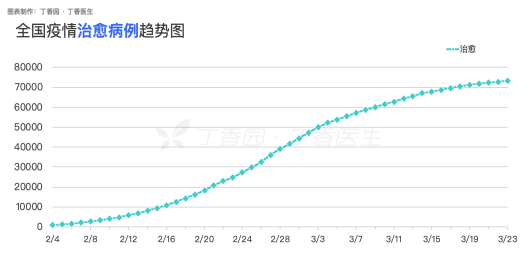

在与新冠病毒肺炎这场没有硝烟的战争中,科研是抗击疫情最核心的“武器制造机”。如果没有科学研究,我们难以想象在2个月内看到治愈人数快速增长,全国9个省份实现确诊人数“清零”(截止到3月23日),在这些数字的背后,科学研究毋庸置疑发挥了重要作用。因为我之前学习的是生物大类专业,再加上习惯对科研稍多一些留意,所以在关注疫情发展的同时,也简单梳理了一些科研抗“疫”的重要研究发现,希望对大家更科学的防疫抗疫有所帮助。

全国疫情治愈病例趋势图(截止到3月23日)